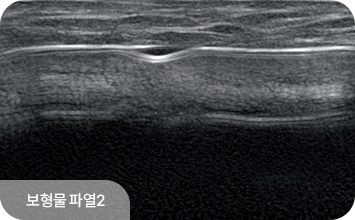

유방 확대술(보형물 삽입) 후에도 초음파 검진은 동일하게 시행할 수 있으며,

보형물 위의 유방 조직을 꼼꼼히 관찰하여 종괴나 이상 소견을 확인합니다.

보형물 자체의 파열이나 누출 여부도 초음파로 평가할 수 있어,

수술 후에도 정기적인 초음파 검진이 중요합니다.